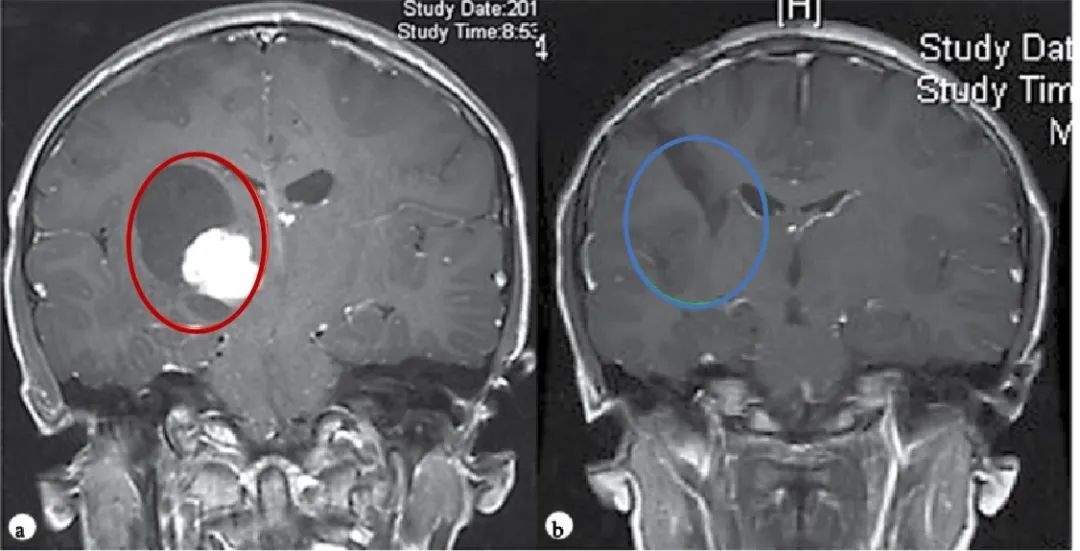

【圖.術(shù)前(a)和術(shù)后(b)顱腦磁共振MR,術(shù)前MR顯示右側(cè)丘腦較大囊實(shí)性占位,膠質(zhì)瘤可能,皮質(zhì)脊髓束(負(fù)責(zé)人體肢體運(yùn)動的神經(jīng)傳導(dǎo)束)受壓,腦室擴(kuò)大,術(shù)后MR顯示腫瘤全切,腦組織復(fù)位,無腦出血、腦水腫等損傷】Rutka教授經(jīng)診斷表示, Dora患上的是一種常見于兒童及青少年的良性膠質(zhì)瘤——毛細(xì)胞星形細(xì)胞瘤。Rutka教授根據(jù)腫瘤生長的具體位置、形態(tài)特點(diǎn),制定了順利的手術(shù)入路方案,并實(shí)現(xiàn)順利全切腫瘤,預(yù)后無并發(fā)癥、沒有復(fù)發(fā),對孩子的成長發(fā)育和智力沒有造成任何影響。